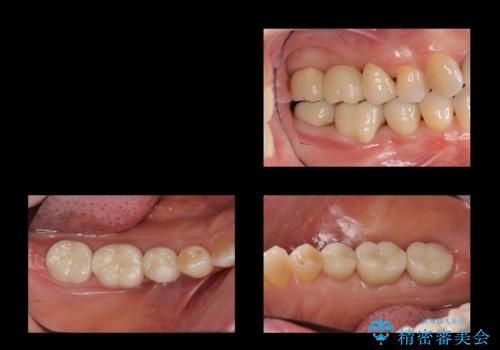

- 56.1万円(右下567 ジルコニアクラウン11万円×3 歯周外科手術APF 15万円 仮歯1万円×3)費用は治療当時の料金となります

歯の高さを出すとかぶせ物(クラウン)がはずれにくくなります。

今回は右下7番が神経のない歯だったため、クラウンにして割れにくくしています。